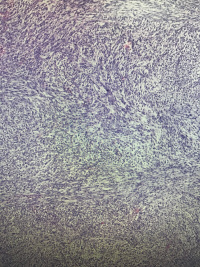

左小腿包块

性别

男

年龄

39

渐增性包块四月,伴破溃流血一月

灰白组织一堆,大小10✖️6✖️4.5,切面灰白灰红,黏液感,

粘液性纤维肉瘤